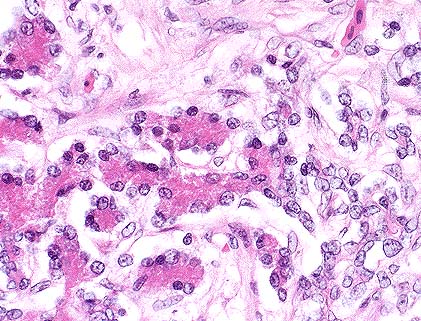

Severe pancreatic atrophy and fibrosis due to zinc toxicosis in an eider duck. (HE, 200X, 97K)

Marked pancreatic acinar atrophy (left) and ductal hyperplasia (right) in a duck with zinc intoxication. (HE, 400X, 64K)

Contributor's Diagnosis and Comments: Pancreas, fibrosis, diffuse, chronic, severe with occasional acinar cell necrosis and acinar disorganization.

The penny removed from the ventriculus of this duck was too severely eroded to read the year of minting, but the gray metallic center indicates that it is composed primarily of a high zinc alloy with a thin coating of copper as are all pennies minted after 1982 (1). Presumably, the duck ingested the penny from a pond in the exhibit, where it may have been tossed by a zoo visitor. Pancreatic fibrosis and necrosis have been associated with zinc toxicity in ruminants (2), chickens (3,4) and ducks (5,6).

AFIP Diagnosis: 1. Pancreas: Exocrine parenchymal loss, diffuse, moderate, with regeneration, fibrosis and ductular hyperplasia, American eider duck (Somateria mollissima dresseri), avian. 2. Serosa: Serositis, fibrinosuppurative, subacute, moderate to severe, with gram-negative bacilli. 3. Omental adipose tissue: Atrophy, multifocal, moderate.

Conference Note: Cases of zinc toxicosis in animals usually result from ingestion of galvanized fence clips or pennies. The histologic and ultrastructural lesions of experimental zinc toxicity in ducklings, chicks, and sheep have been described.

Several distinct syndromes have been reported following ingestion of zinc-containing objects. A zinc-induced hemolytic anemia has been described in a puppy following ingestion of pennies. An experimental study in sheep suggests that the primary lesion in zinc toxicosis is pancreatic ductular necrosis. The early lesions described in sheep include necrosis of the pancreatic ductular epithelium, periductular inflammation, and interlobular fat necrosis, followed by edema, lobular cystic change, atrophy, fibrosis, and ductular hyperplasia. Necrotizing enteritis and renal tubular necrosis have also been reported in birds.

Ultrastructurally, pancreatic exocrine cells have reduced numbers of zymogen granules, distended rough endoplasmic reticulum, many small cytoplasmic electron dense bodies, large autophagic vacuoles, and necrosis. These lesions reflect interference with pancreatic protein synthesis and membrane integrity.